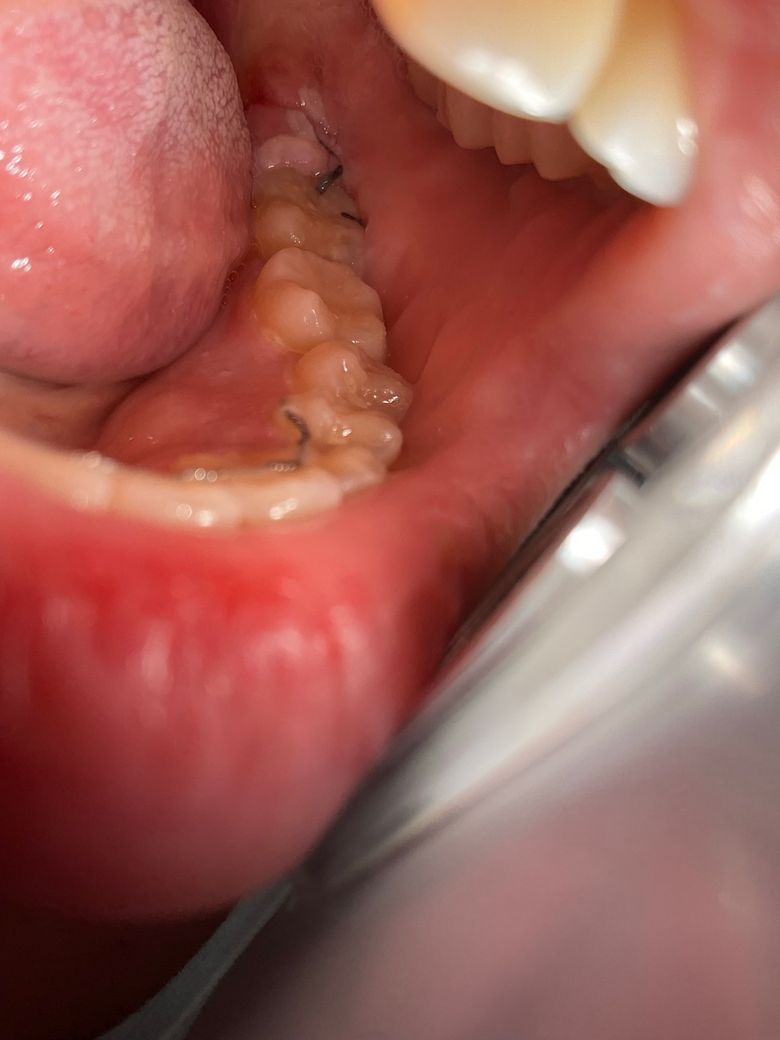

(사진O) 사랑니 발치 후 3-4일차 치유과정 괜찮나요??

발치 부위쪽엔 하얀색 막?인지 있구요

저 하얀색 막?이 무엇인지와 언제쯤 없어지는지? 궁금합니다

그리고 맨 뒷부분 잇몸은 아직 부어서 빨갛습니다

• 1번 째 사진

사진으로 봤을 경우에는 크게 문제가 없어 보입니다. 사랑니를 발치하고 나면 발치한 부위에 가피등이 형성되면서 하얀색 막이 보일 수 있습니다.

발치 부위에 생긴 건 염증조직으로 보입니다 발치 부위 위생관리 잘해주시기 바랍니다 가볍게 가글하면서 음식물 낀거 잘 빼주어야 합니다